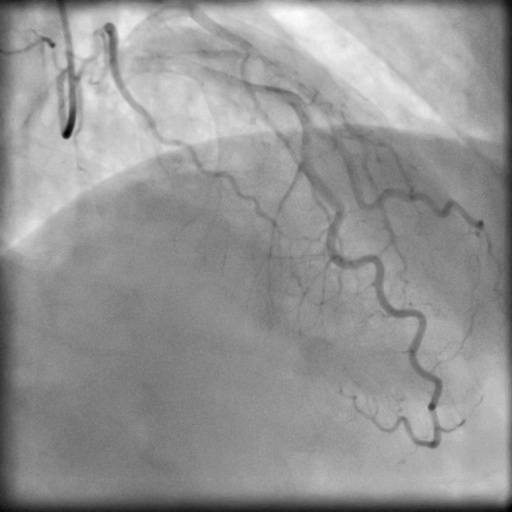

4.1 XACV Dataset

We collect 111 complete records of coronary artery X-ray videos, encompassing the injection, flow through the blood vessels around the heart, and dissipation of the contrast agent. Subsequently, we establish the XACV (X-ray Angiography Coronary Video) dataset. Each video consists of varying numbers of high-resolution coronary artery X-ray images. We invite experienced radiologists to annotate the vascular regions, focusing on one or two frames where the contrast agent is most prominent in each video. The XCAD dataset contains only a single image, and the CADICA video dataset does not provide corresponding ground truth. Therefore, in the following experiments, we conduct all the analyses on our collected XACV dataset and the corresponding GT for each sequence. In Figure 5, we show that compared to other publicly available datasets, XCAD [33] and CADICA [19], our dataset exhibits finer annotations in the vascular regions, providing an advantage for future related tasks. The development and use of our dataset have been approved by our institution’s IRB.